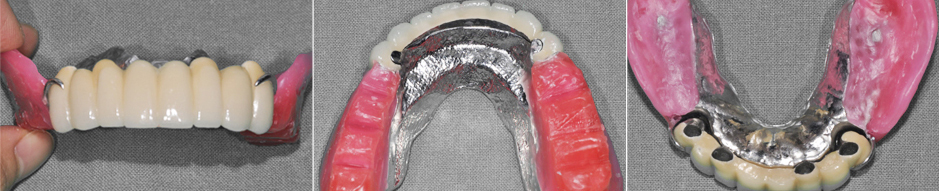

02 고정식 임플란트 틀니

전체 임플란트에 비해 경제적이며 발음 문제로 상악보다는 하악 틀니에 주로 사용됩니다. 입 천장이 뚫려있어 이물감이 적고 틀니가 탈락되지 않아 편안합니다.

👤 임플란트 오버덴쳐 치료 CASE

틀니/오버덴처 제작

수술 전 | |

틀니 제작 | ![]() |

수술 후 | ![]() |